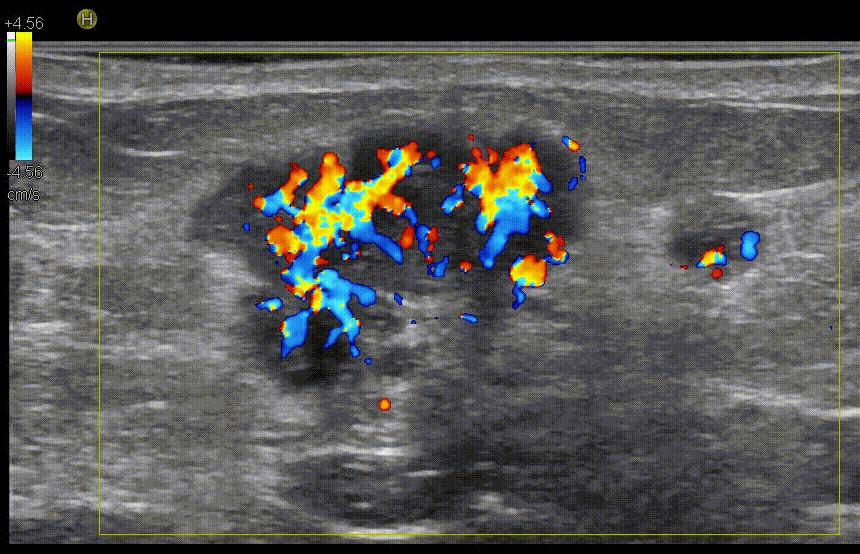

Допплеровский режим определяет кровоток. Важная технология, которая позволяет врачу увидеть сосудистую сеть патологического образования без введения контрастного вещества. Конечно, Допплер не такой чувствительный режим, как контрастирование, но в большинстве случаев он дает важную информацию и способствует раннему выявлению рака.

Рис.8 Эхограмма гиперваскулярного рака молочной железы